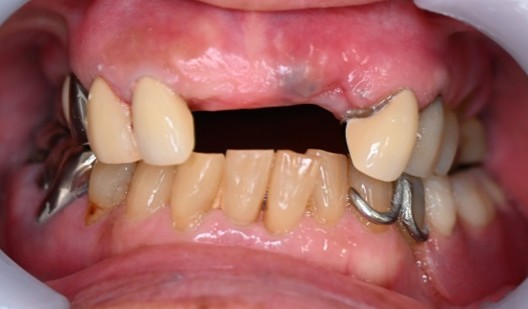

Before

【義歯を外したところ】